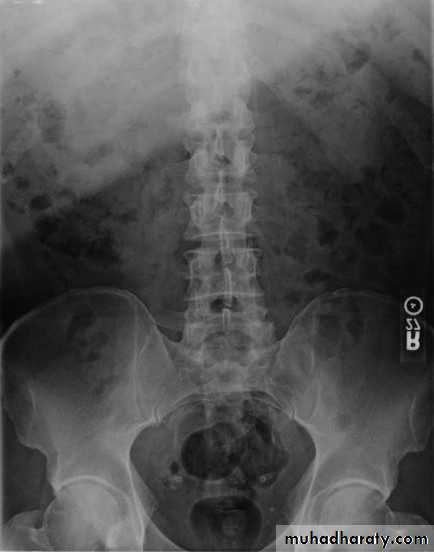

• Intravenous (Excretory) Urography

• Preliminary

• Immediate• Compression

• 5 minutes

• Release

• Post -micturation

• Check the Kidneys: outline, size, site

• Check the calyces: cupped• Check renal pelvis and ureter

• Check the bladder